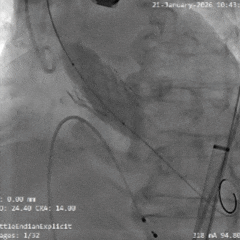

术中影像

根部造影

瓣叶活动差,可见明显反流,猪尾导管测量跨瓣压差约50mmHg

20mm球囊预扩

微腰微漏,左右冠均显影

造影确认瓣环与瓣膜位置

瓣膜0位初始定位释放,展开过程微微下移

全展开位造影评估

瓣膜呈直筒型,微腰,大弯侧约瓣下3mm,少量反流,冠脉显影

瓣膜无张力脱钩

植入后造影评估

瓣膜位置合适,可见少量反流

多角度造影评估

瓣膜形态可,冠脉显影,猪尾测量压差为0